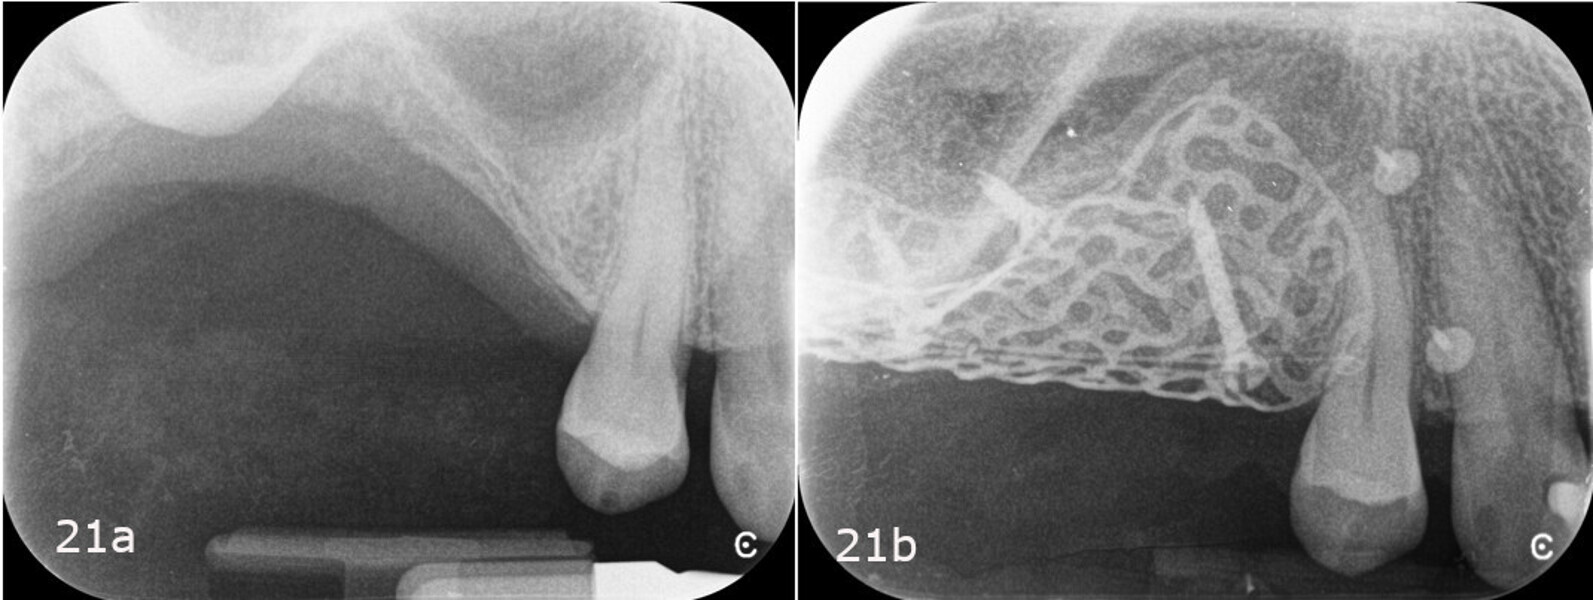

As it is a tissue extremely rich in pluripotent cells, capable of differentiating to promote healing by first intention of the treated area, the buccal pad of fat was isolated and advanced before closing the primary flap to reduce the risk of exposure and infection of the underlying mesh (Fig. 19).17 Finally, the buccal and vestibular surgical flaps were sutured using a double line of sutures, the first consisting of horizontal mattress sutures and the second of single or double interrupted sutures (GLYCOLON, Resorba; Figs. 20a & b; 21a & b).